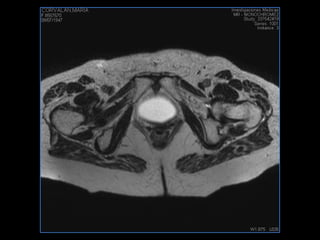

PROTOCOLO pelvis SAG T2, Y FAT SAT (FINOS) AXIAL T1  AX FAT SAT CON   GADOLINIO :  AX T1 Y COR T1 SAT: NO  FASE: RL THK: 3MM  COIL:  GAP: (FACTOR 1.4) 1MM FOV: 40 CM NEX:2 SINCRONIZACION RESPIRATORIA EN 3 O 4 CICLOS ALE

resonancia de abdomen